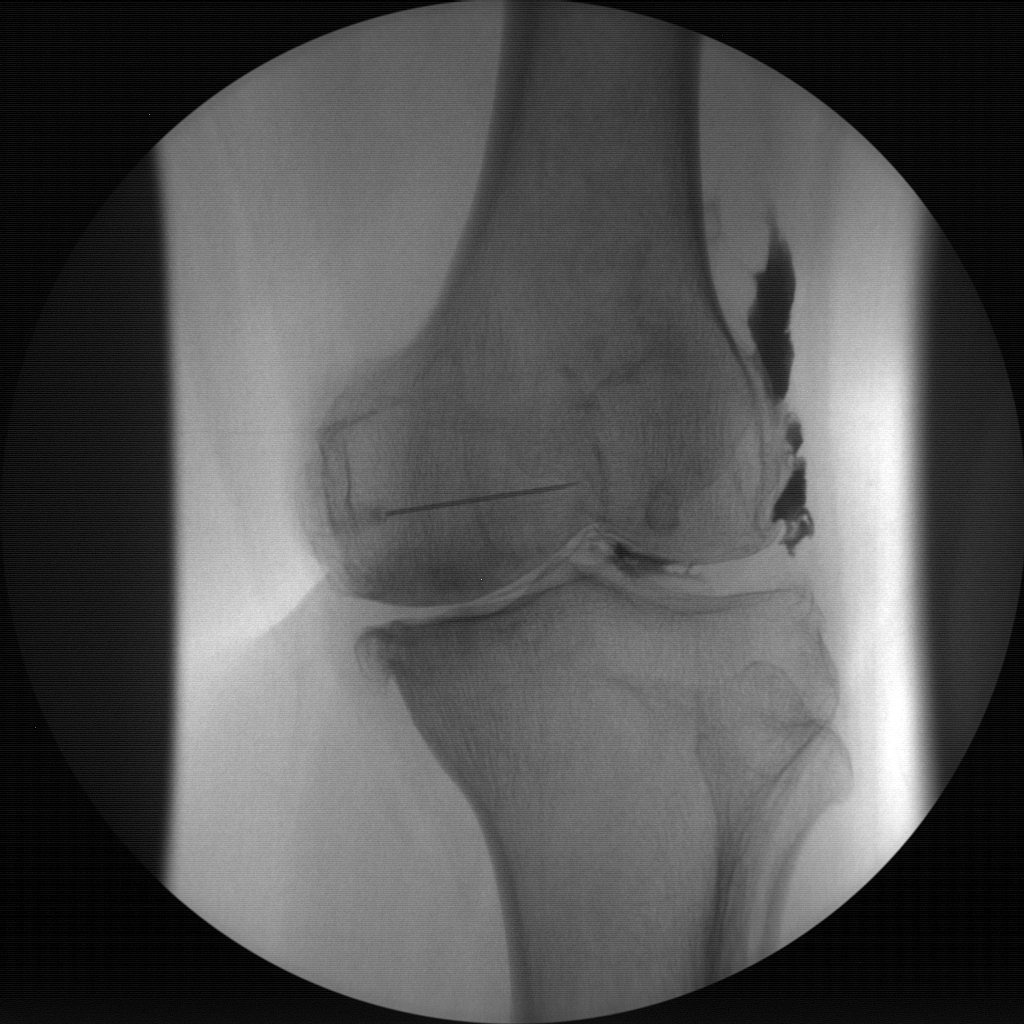

Joint Injections

Skan-C proves highly effective in performing joint injections, a procedure commonly used to administer pain-relieving medication directly into the affected joints, such as the knee, shoulder, or hip.